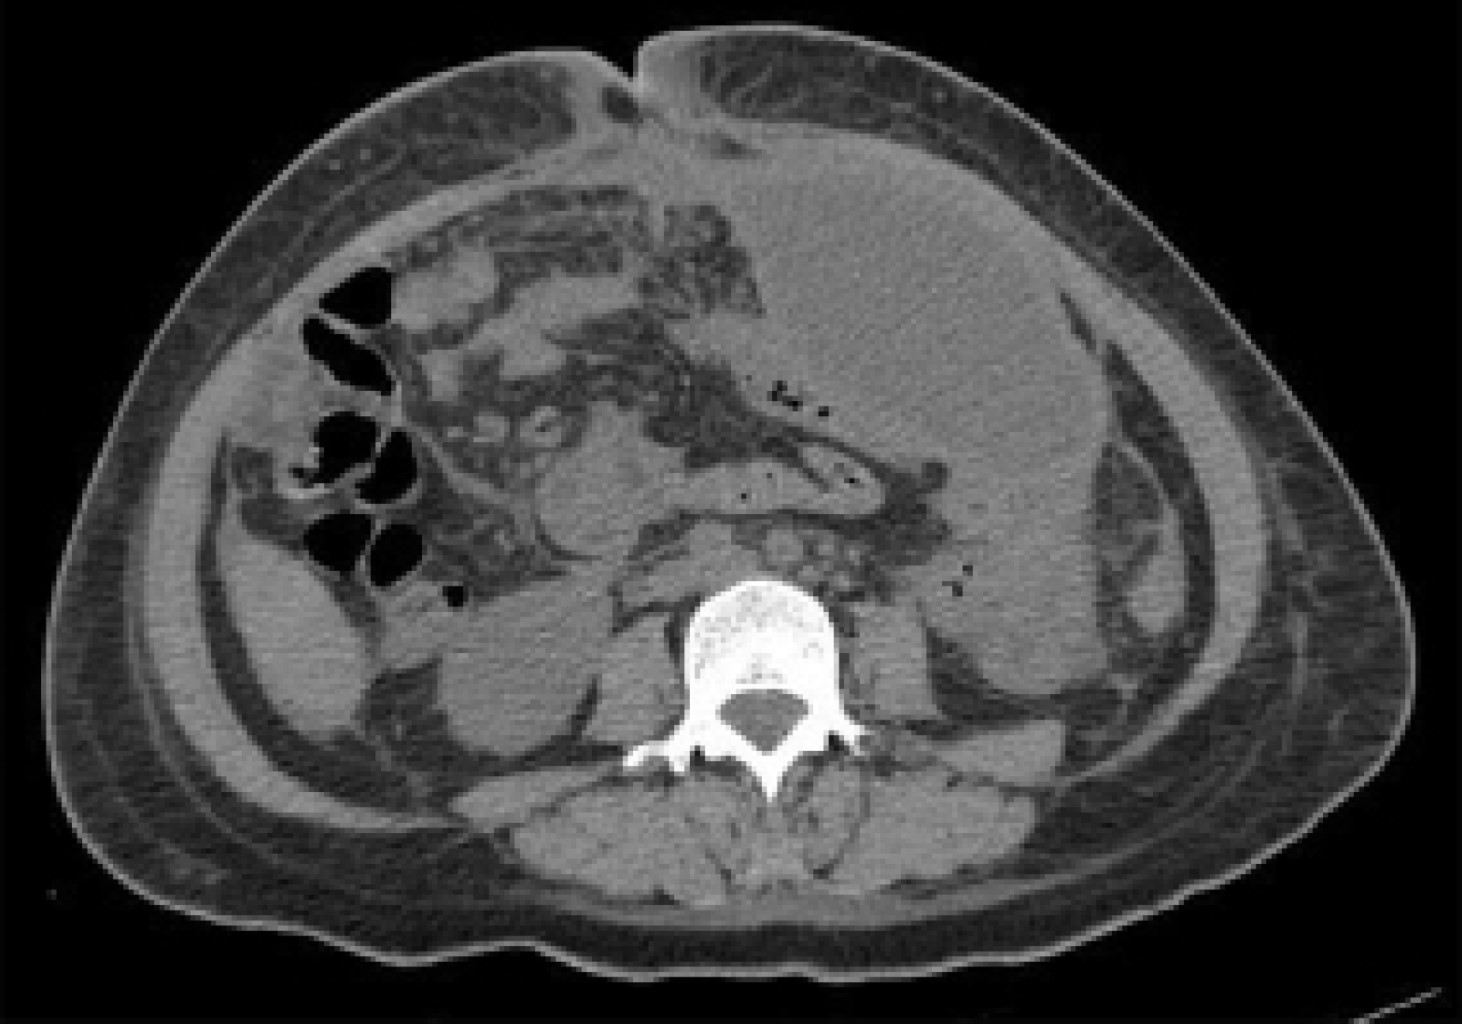

A 40-year-old female patient had four gestations, three deliveries, and a history of aortic valve stenosis since 2017 with surgical management based on valve prosthesis placement and use of acenocoumarin until the diagnosis of her last pregnancy, during which oral the anticoagulant drug was suspended, and enoxaparin was started. She started her current condition when she was admitted to the obstetrics service with a gestational age report of 28.5 weeks of gestation (SDG) by the last menstrual period and 29.4 by fetometry. Preeclampsia was diagnosed with severe data, so it was decided to perform a Kerr cesarean section and bilateral tubal occlusion with Kroener technique, reporting 350 cm3 of bleeding, obtaining a single live male product of 31.5 weeks by Capurro, with an Apgar score of 7/8, and with cleft lip and palate. She was discharged on the fifth day, requiring a transfusion of blood products in her immediate postoperative period. Twenty-one days later, she was readmitted due to abundant and fetid bleeding through the surgical approach; wound healing was performed, and an abdominal wall defect was evidenced, so it was decided to perform an ultrasound, with findings of a defect in the anterior abdominal wall in the cephalic portion of the wound through which intestinal loops protrude (Figures 1 and 2). In an abdominal computerized tomography scan, a heterogeneous non-measurable collection was identified in the middle and caudal third of the wound at the level of the subcutaneous plane, as well as a thick-walled collection in the pelvic cavity and left iliac fossa (Figure 3).

Figure 3